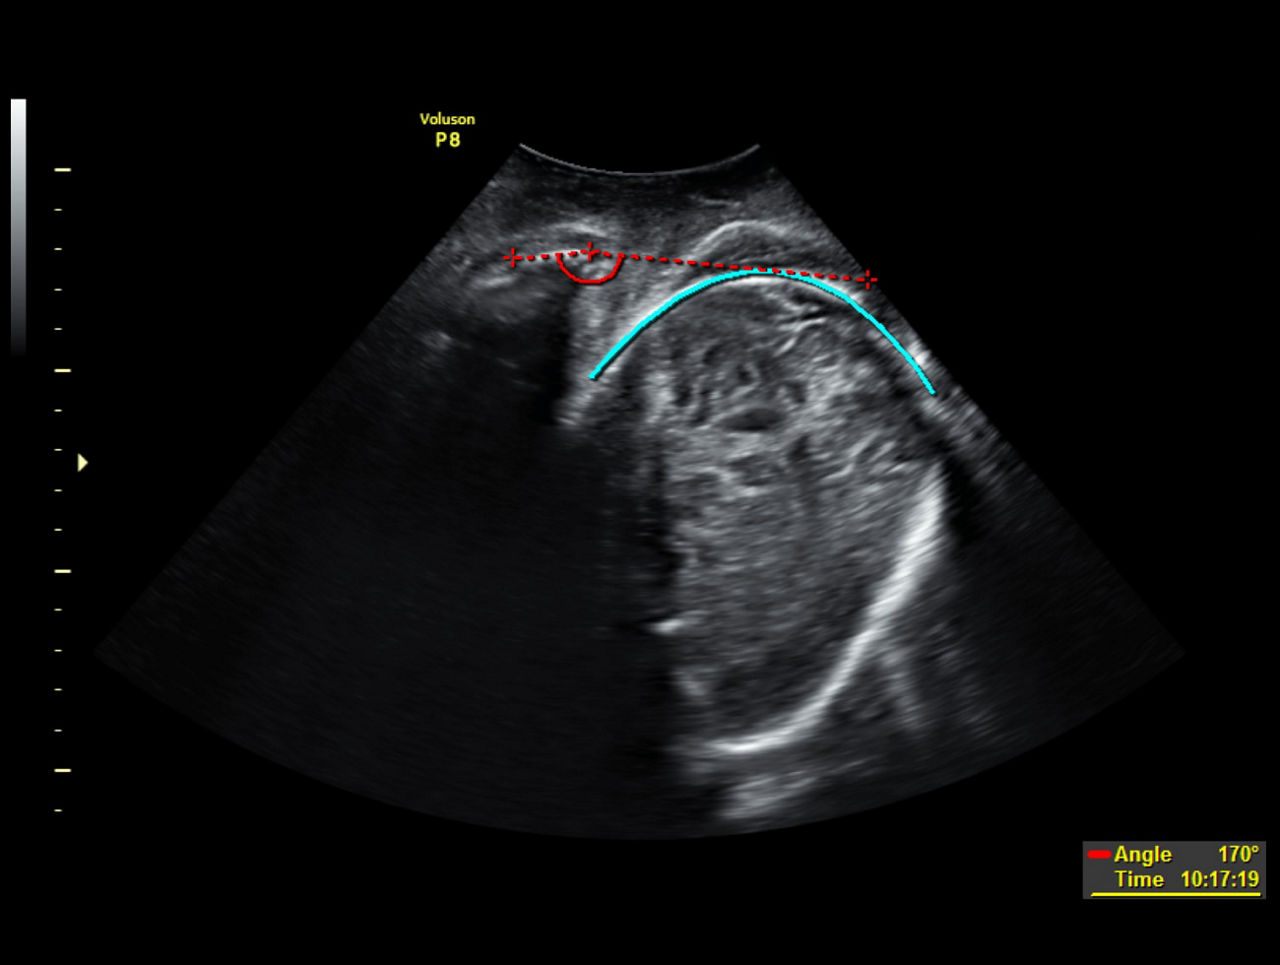

SonoL&D

Automated technology that monitors and documents labor to help evaluate second-stage labor progression.